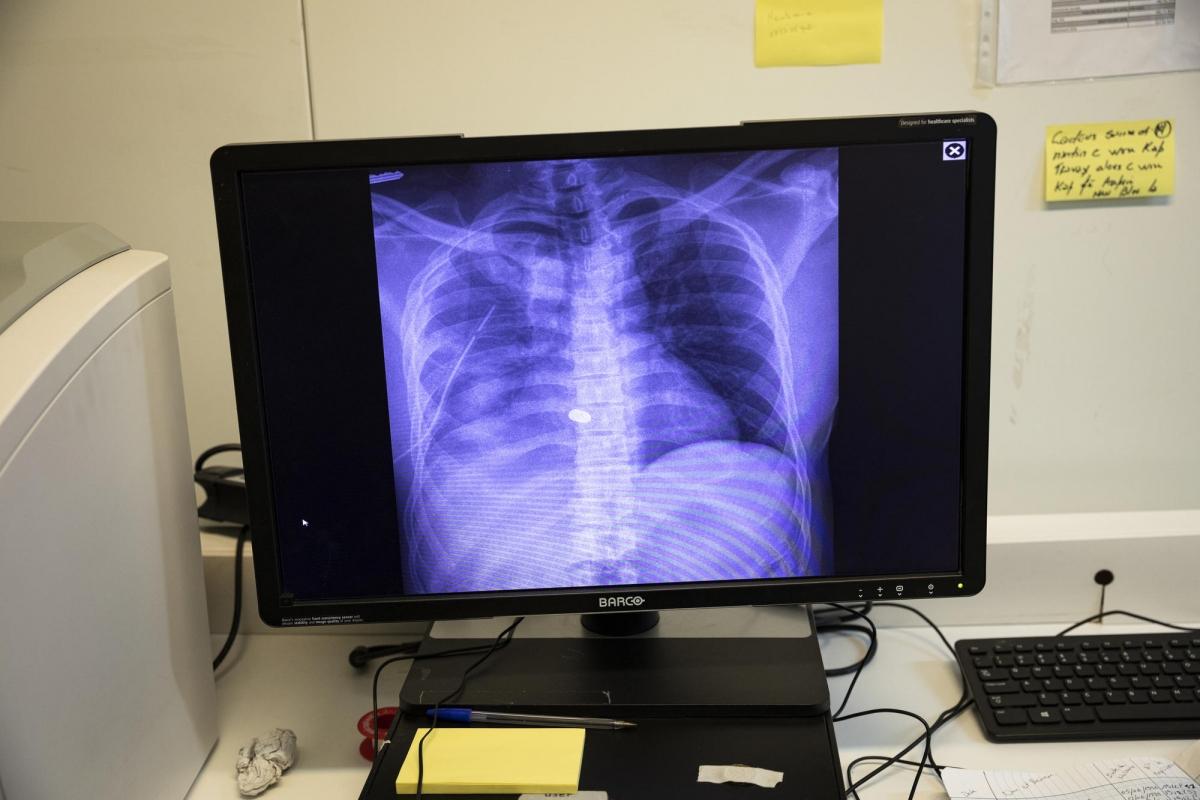

Radiographie du thorax de Dourgé, 37 ans. Il se trouve aux soins intensifs du service de traumatologie de l'hôpital de Tabarre depuis 5 jours. Agent de sécurité, il est arrivé aux urgences le 5 décembre 2019, suite au braquage de la banque pour laquelle il travaille à Croix-des-Missions. Avant de prendre la fuite les assaillants lui ont tiré dessus à deux reprises. Une des deux balles s’est logée dans sa cage thoracique. Trop près de la colonne vertébrale, cette dernière ne peut être retirée et lui paralyse la jambe droite. Père de 2 enfants, il a commencé à travailler comme agent de sécurité 4 mois auparavant, mais la crise économique et politique actuellement en cours dans le pays l'empêchait parfois de se rendre sur son lieu de travail. © Leonora Baumann